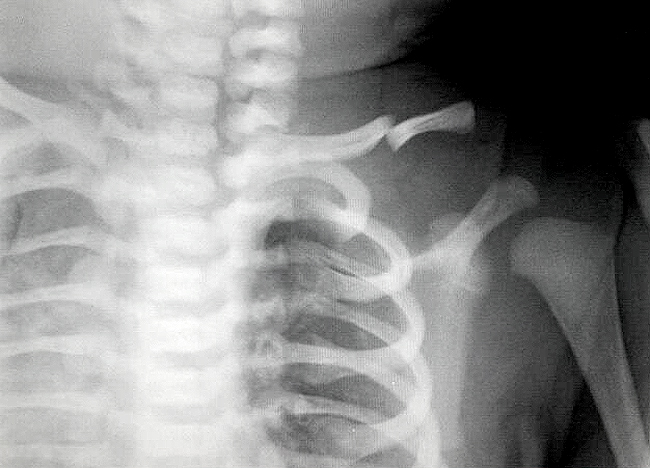

Детям, особенно в раннем возрасте, рентгенологическое обследование проводят по крайне редким показаниям. Если нет смещения отломков, и нет признаков повреждения нервов и сосудов, проводить рентген не обязательно.

Перелом ключицы у новорожденных — это достаточно распространенное явление, которое может вызывать беспокойство у родителей. Врачи отмечают, что такие травмы часто происходят во время родов, особенно при использовании инструментов или при затрудненных родах. Несмотря на это, в большинстве случаев перелом заживает самостоятельно без необходимости хирургического вмешательства.

Специалисты подчеркивают, что важно своевременно обратиться к врачу, если у ребенка наблюдаются признаки боли или ограничение движений. Рентгенография поможет подтвердить диагноз и исключить другие травмы. Врачи рекомендуют родителям следить за состоянием малыша и обеспечивать ему комфортные условия для восстановления. Важно помнить, что при правильном уходе и соблюдении рекомендаций специалистов, новорожденные быстро восстанавливаются и продолжают развиваться без последствий.